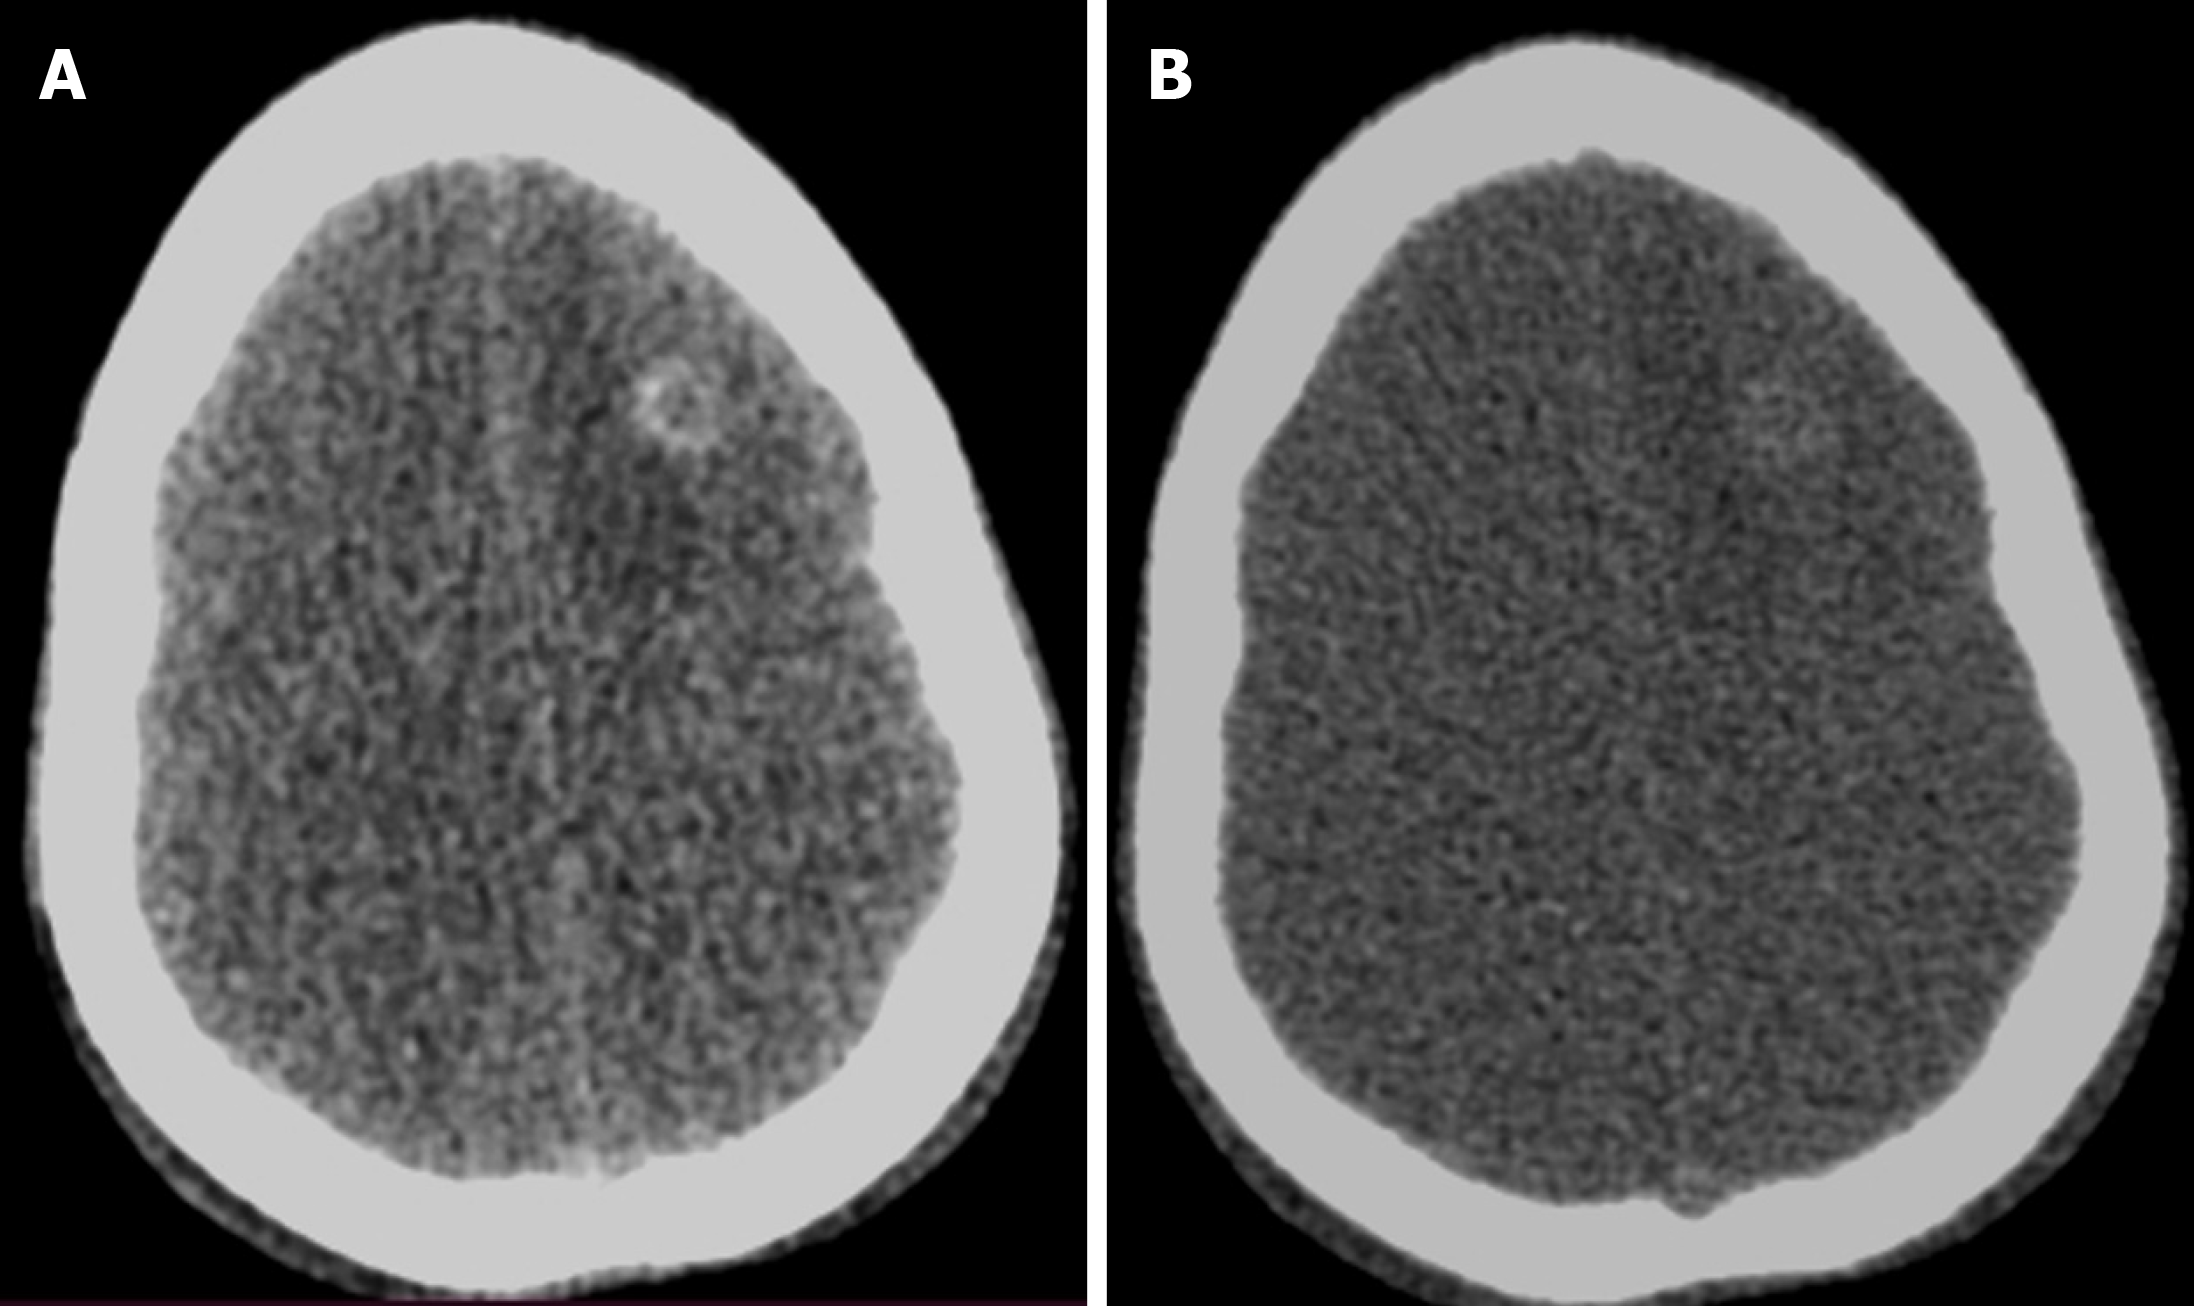

Figure 3 An 11-year-old female with generalized tonic-clonic seizure and post-ictal drowsiness.

A: Axial section of contrast-enhanced CT head image at 70 kV showed better contrast enhancement of the wall in the ring-enhancing lesion with perilesional edema; B: There was only subtle contrast enhancement in the image obtained at 150 kV.